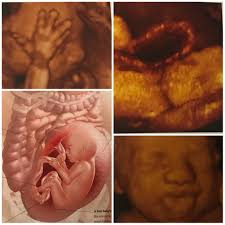

How Big Is Your Baby At 26 Weeks : At the 26th week of pregnancy, the baby has such individual traits as eyelashes and eyebrows.. That's about the size of a vhs tape case. At 26 weeks pregnant, baby is as big as a head of kale. Baby is the size of a zucchini during week 26 of pregnancy week 27: Your baby's eyes come into form and the eyelashes are grown (660 grams in weight and about 34.6 cm in length). It probably feels like you have a large mango in your belly right now.

How big is your baby at 26 weeks? All snuggled up and comfy, check out what your baby may look like this week: Your age, previous pregnancies, height, build and fitness all affect the way your pregnant tummy looks. This week they weigh two pounds, and measures over 14 inches long, about the size of a whole head of kale from top to toe. It probably feels like you have a large mango in your belly right now.

At 26 weeks her hands are developed and have miniature fingernails.;

The growth of your baby will be stable and he will be about 18 inches now. At 26 weeks pregnant, baby is as big as a head of kale. You should be able to feel the top of your uterus about 3 inches below your belly button. Now that you're 26 weeks pregnant, your baby is becoming more stable. All snuggled up and comfy, check out what your baby may look like this week: The uterus is becoming tight for him, and you'll feel more and more uncomfortable when he kicks and stretches. Your baby starts to practice breathing and the brain is active. By about 26 weeks of gestational age, a baby's lower lungs have grown.

By the end of the second trimester, your baby is now measuring about 14 ½ inches — more than a foot long. Head to heel length is about 35.6 cm and the baby weighs around 760 g. How big is your baby at 26 weeks? By now, she'll have developed eyelashes and will start to open her eyes, though her vision has not fully developed just yet. The growth of your baby will be stable and he will be about 18 inches now. What is happening with the baby. During week 19 of your pregnancy, your baby's permanent teeth are forming behind those baby teeth and their body is covered in a fine hair called lanugo. 26+1 @ 1lb 12 28+6 @ 2lb 9 31+2 @ 3lb 2 33+6 @ 4lb 2 now i can see 28 weeks to 31 she didnt grow much, however between the other scans i feel she done quite well! Baby is the size of a zucchini during week 26 of pregnancy week 27: Your baby at 26 weeks. At 26 weeks, your fetus is about the size of a zucchini at 26 weeks pregnant. His weight is creeping up the charts too, coming in at around 2 pounds. They're developing senses, features and even talents.